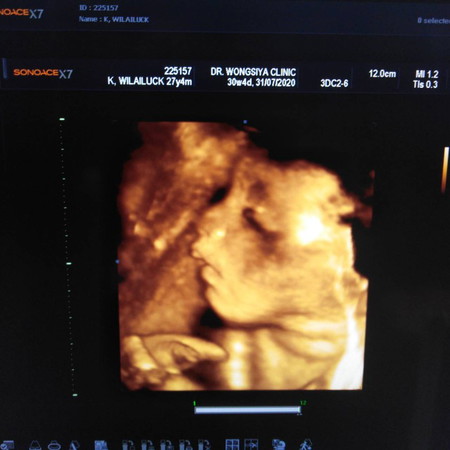

นิ้วมือของน้องปกติไหมค่ะเรามองเหมือนนิ้วติดกันแม่ๆช่วยดูให้หน่อยค่ะ

ปกคิค่ะเเม่ ถ้าผิดปกติหมอคงจะเเจ้งให้ทราบ ซาวด์4มิติก็เเบบนี้เเหละค่ะ ภาพเป็นตะปุ่มตะป่ำ